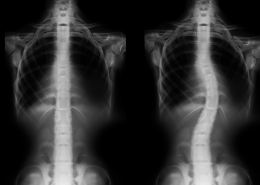

- Scoliosis, kyphosis

- Hunchback

- Pediatric spinal disorders

- Spinal deformities in adults